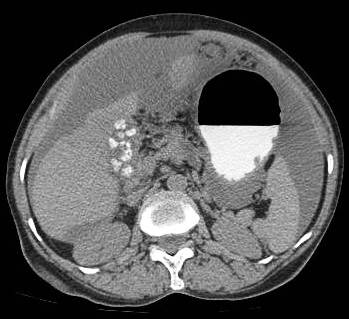

Common patterns of carcinoma gallbladder

Three patterns have been described on ultrasonography (US). The gallbladder fossa is replaced by a heterogeneous mass (figure 1) with internal areas of necrosis; or there may be diffuse, irregular, and asymmetrical wall thickening (Figure 2); or less commonly, a polypoidal, fungating intra-luminal mass is seen. Correct preoperative diagnosis has improved considerably with the use of newer imaging techniques [6-8]. Majority of cases when diagnosed, are no longer resectable (Figure 3) [9-11].

Figure 2: diffuse infiltrative carcinoma of the gallbladder with irregular wall thickening and invasion of liver parenchyma. Medially the plane with second part of duodenum is invaded. Inferiorly right perinephric fat plane invaded